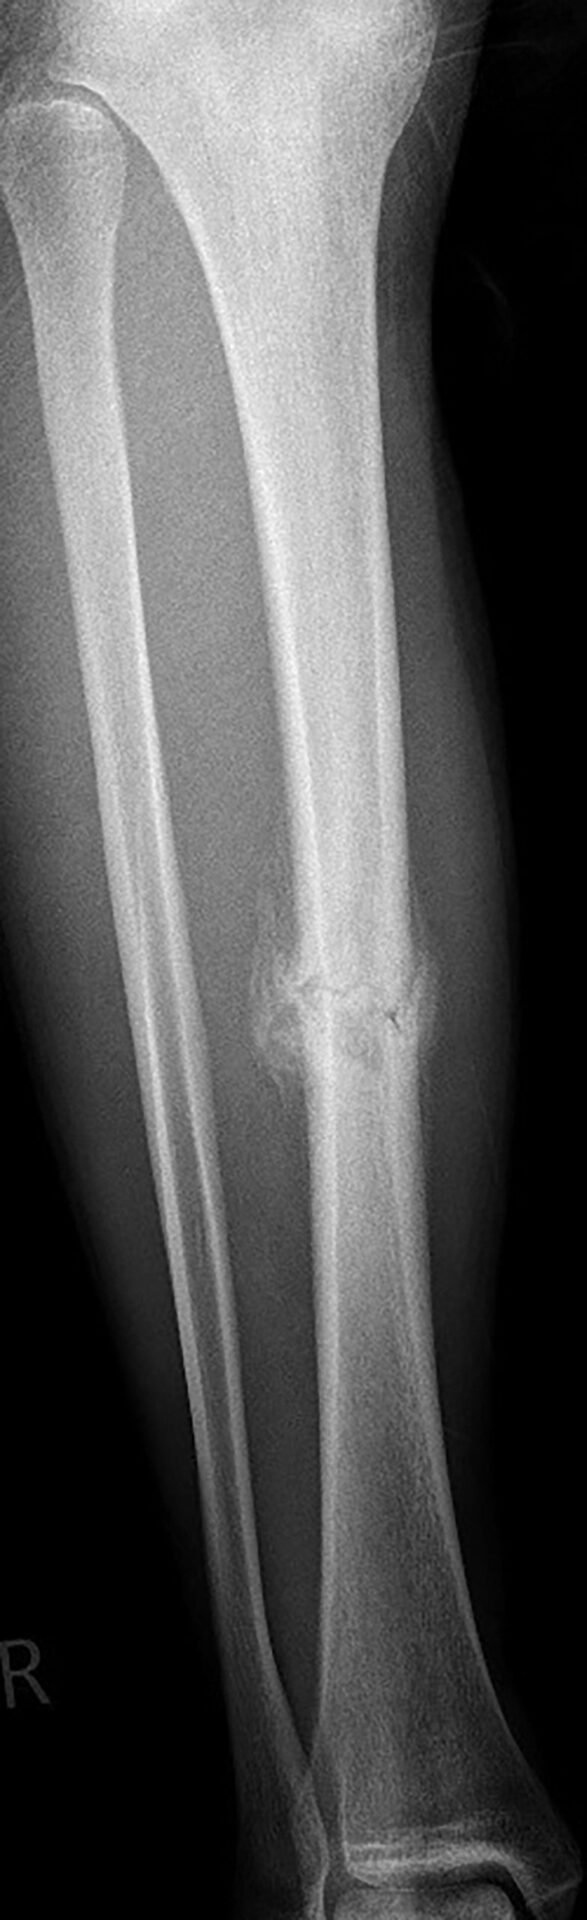

Der Spieler wurde stationär aufgenommen und erhielt neben Antikoagulationstherapie und Novalgin eine Oberschenkelgipsschiene und Unterarmgehstützen. Mit verschiedenen Ärzten evaluierte der Spieler Pro und Contra operativer und konservativer Therapie. Nach zwei Tagen entschied er sich gegen eine OP und wurde nach Hause entlassen. Voraussetzung hierfür war konsequente Ruhe, Hochlegen des Beines und eine wöchentliche Röntgenkontrolle, um Achsabweichungen im Knochenheilungsprozess erkennen zu können. Ab der 2. Woche begann die Physiotherapie. Um den Abtransport der Schwellung, welche sich deutlich im Sprunggelenk und Fuß abgelagert hatte, zu unterstützen, wurde der Unterschenkel mit Grifftechniken aus der manuellen Lymphdrainage behandelt. Das Bein wurde dabei nicht aus der Schiene bewegt. Außerdem benutzte der Spieler eigenständig ein EMS-Gerät, welches er hauptsachlich auf den Quadriceps applizierte. Nach drei Wochen erhielt der Spieler eine Sarmiento-Brace, welche in einem speziellen Orthopädiefachgeschäft maßangefertigt wurde. Diese sollte er weitere drei Wochen tragen. Parallel dazu lag der Fokus weiterhin auf Krafterhaltung der Rumpfmuskulatur und Resorptionsförderung der Schwellung. Nach sechs Wochen konnte der Spieler mit 15 kg die Teilbelastung starten. Als er nach sechseinhalb Wochen mit den Gehstützen auf nassen Badfliesen ausrutschte, kam es zu einer erneuten kurzfristigen Schmerzprovokation und deutlichen Schwellungszunahme in der ventralen Tibia. Das Röntgenbild zeigte keine Verschiebung der Fraktur (Abb. 2). Jedoch wurden Zeichen einer Refrakturierung wurden im Röntgenbild zwei Wochen später sichtbar (Abb. 3). Schwellung und Schmerz waren inzwischen wieder deutlich reduziert und es konnte weiter langsam mit der Aufbelastung auf 30 kg Teilbelastung gestartet werden. Zusätzlich erhielt der Spieler ein Exogen Gerät zur Ultraschalltherapie zu Hause, welches er täglich 20 min verwendete. Zehn Wochen post-injury, damit vier Wochen post re-injury, konnte der Spieler die komplette Belastung wieder aufnehmen. Die Verwendung des Gerätes läuft aktuell täglich über 20 min weiter und unterstützt den Spieler nach subjektivem Empfinden deutlich bei der weiteren Behandlung. Zusätzlich zu der Behandlung wurde dem Spieler während des gesamten Verlaufs eine Substitution von Vitamin D + Vitamin K empfohlen.